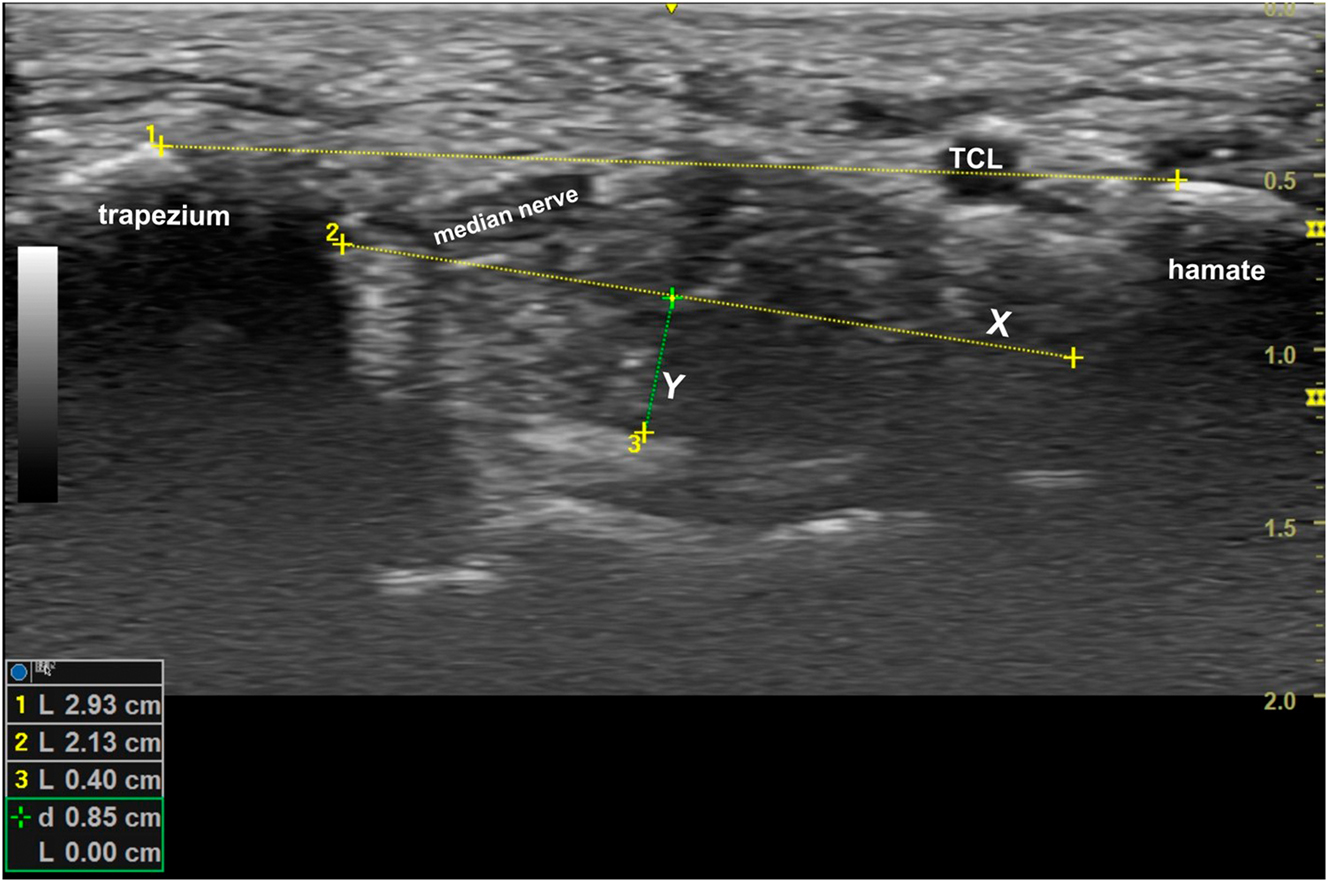

Immediately following the manipulation, each participant was placed back into their splint, and five more measurements made of the carpal tunnel dimensions which were then averaged. The ultrasound measurements were made with a GE Versana Active laptop utilizing a linear probe by a single physician (the corresponding author) who was blinded to which participants were in the control group and OMT groups. The length of the transverse carpal ligament was measured from the hyperechoic peaks of the hamate hook and trapezium tubercle. At this same level, the greatest width of the carpal tunnel and a right-angle distance from this line to the floor of the tunnel were measured. The area of the tunnel at this cross-section was estimated as an ellipse (Figure 3). The study employed a two-group, pre-/postmanipulation design to evaluate the anatomical changes resulting from the DCA-ME OMT manipulation compared to those following the control sham manipulation.

The length of the transverse carpal ligament was measured on a short-axis ultrasound of the carpal tunnel at its most restrictive site beneath the transverse carpal ligament running between the hook of the hamate and the tubercle of the trapezium. The greatest width of the carpal tunnel was also measured (X), and a right-angle distance from this line down to the floor of the tunnel (Y) was calculated. The area was estimated by multiplying 1/2(X) (Y) (π).